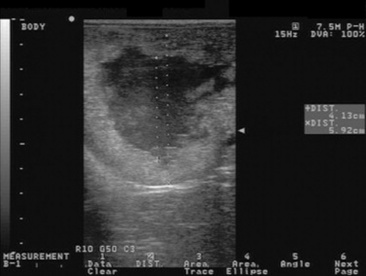

Ovulation failure is a normal physiologic event for the mare during the spring and fall transition periods, but it may also occur occasionally during the physiologic breeding season. Persistent anovulatory follicles (PAFs) may be quite large (5 to 15 cm in diameter), persist for up to 2 months, and result in abnormal estrous behavior and prolonged interovulatory intervals.89 The cause of ovulation failure has been suggested to be endocrine in nature. Absence of sufficient pituitary gonadotropin stimulation to induce ovulation, or insufficient estrogen production from the follicle, has been proposed as a possible mechanism. PAFs were reported in a recent study to occur in approximately 8.2% of estrous cycles.67 The formation of an anovulatory follicle was preceded by development of normal endometrial folds or edema in 78.3% of these cases. Initial growth patterns of follicles destined to become anovulatory were usually normal, and the first indication of a problem was the detection of echogenic particles within the follicular fluid. The incidence of PAFs was also found to increase with age.

PAFs may contain blood and have been termed hemorrhagic anovulatory follicles., The hemorrhage can be detected ultrasonically as scattered free-floating echogenic spots within the follicular fluid. The follicular fluid may form a gelatinous, hemorrhagic mass within the follicular lumen. Ultrasonographically these structures may contain echogenic fibrous bands traversing the follicular lumen (Fig. 43-5). A thickening of the follicular wall may be observed in anovulatory follicles. This thickening is often associated with luteinization of the follicular wall, and 85.7% of PAFs were found to be luteal structures based on elevations in plasma progesterone concentrations.67

image

Fig. 43-5 Transrectal ultrasonographic image of a persistent anovulatory follicle in a mare.